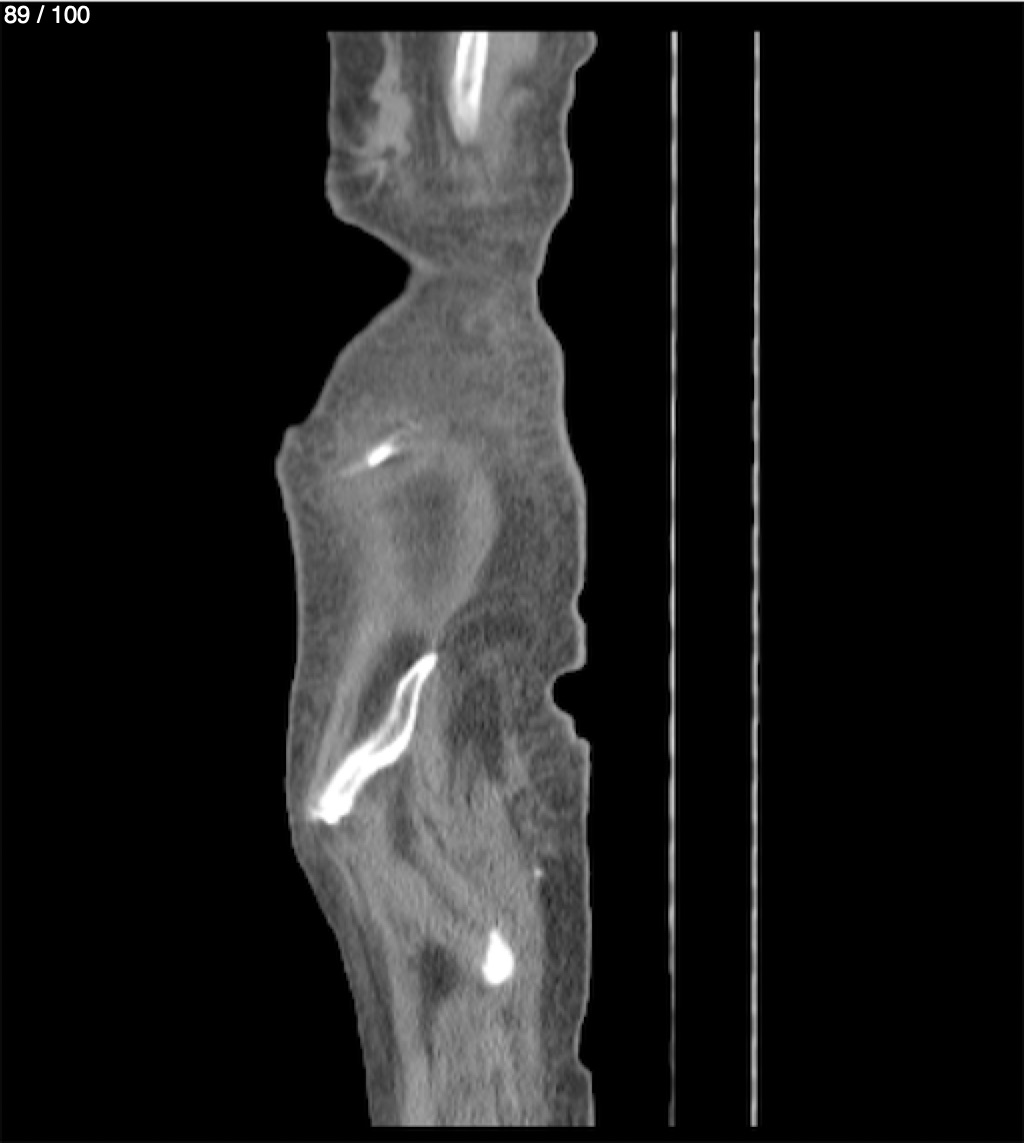

Hilda Geronimo Mendez 60A - T.C Abdomen Simple